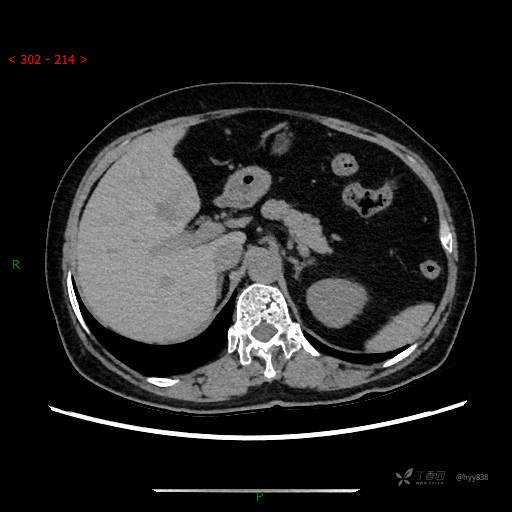

讨论:病变性质?